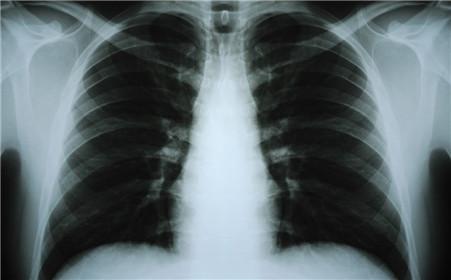

胸部x线,这么看你简单多了

气液平面x线图片

气胸x线胸片图解